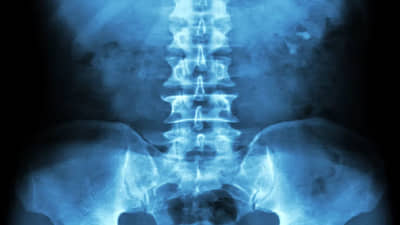

వివరాల్లోకెళ్తే.. అల్లూరి సీతారామరాజు జిల్లా కూనవరం కోతులగుట్ట ప్రాథమిక ఆరోగ్య కేంద్రంలో దారుణం జరిగింది. కుళ్లపాడు గ్రామానికి చెందిన షేక్ జాస్మిన్‌కి కుటుంబ నియంత్రణ ఆపరేషన్‌లో దూది, చిన్న వైరు కడుపులో వదిలేశారు డాక్టర్లు. మే 27వ తేదీన కూనవరం ప్రభుత్వ ఆసుపత్రిలో సదరు బాధితురాలు కుటుంబ నియంత్రణ ఆపరేషన్ చేయించుకుంది. ఇక ఆపరేషన్ అయినప్పటి నుంచి ఆమె తీవ్రమైన కడుపు నొప్పితో బాధపడుతోంది. దీంతో చేసేదేమిలేక భద్రాచలం‌లోని ప్రైవేట్ ఆసుపత్రిని ఆశ్రయించింది బాధితురాలు. అక్కడ వైద్య సిబ్బంది స్కానింగ్‌ చేసి.. ఎక్స్‌రే తీయగా.. ఆమె కడుపులో దూది, వైరు ముక్క ఉన్నట్టు గుర్తించారు. హుటాహుటిన డాక్టర్లు ఆపరేషన్ చేసి.. వాటిని బయటకు తీయడంతో.. ప్రాణాపాయస్థితి నుంచి బయటపడింది బాధితురాలు. కాగా, తనకు ఇలా చేసిన కోతులగుట్ట ప్రాథమిక ఆరోగ్య కేంద్రం వద్ద సదరు బాధితురాలు.. న్యాయం కోసం ఆందోళనకు దిగింది.